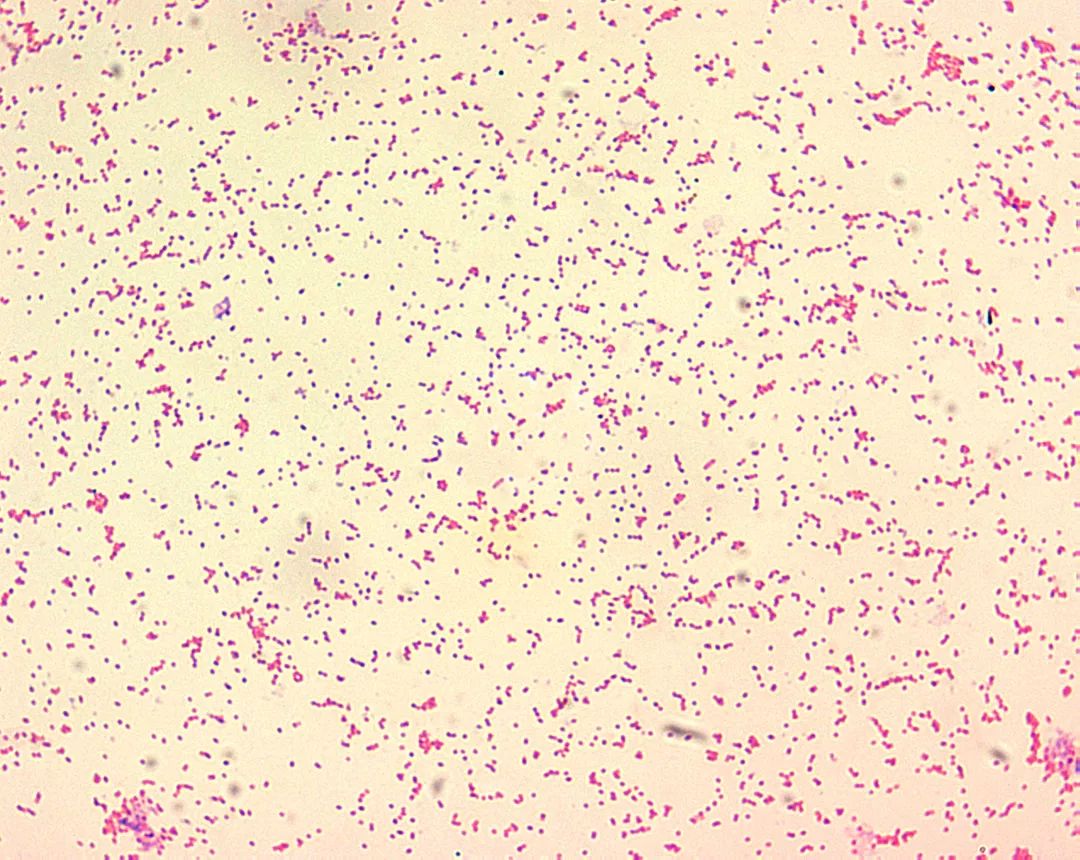

布鲁菌

图片尺寸612x816